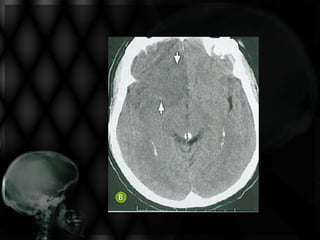

• Paciente de 78 anos, hipertenso, apresenta início súbito

de perda da força muscular à direita, com desvio de rima

bucal e sinais piramidais também à direita. É incapaz de

deambular e sua fala está arrastada e praticamente

ininteligível há 6 horas;

• Solicitou-se TC de crânio.

Não se visualiza nesta TC de crânio:

Edema cerebral

Sangramento na periferia do 4º ventrículo

Hipodensidade frontal direita extensa

Foco de sangramento no interior da área

isquêmica